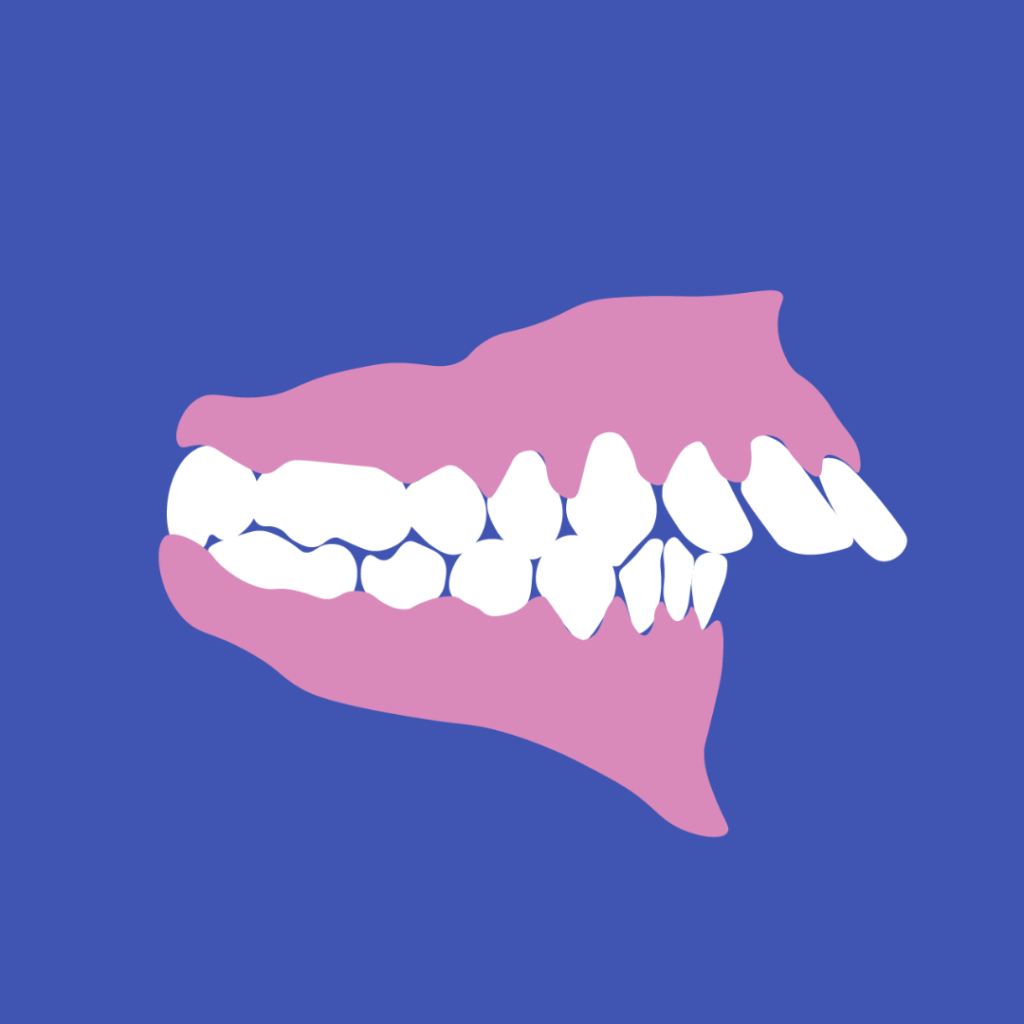

Riconosci il tuo sorriso in uno di questi?

Mesiocclusione:

3 ͣ classe scheletrica